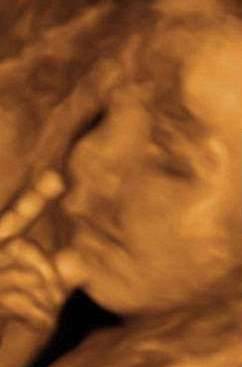

▼这个宝宝不愿意父母太早看到自己,所以将脸埋在手臂中。